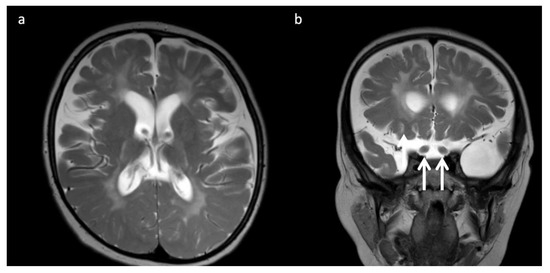

Figure 6.

Three-year-old child with Krabbe disease and frequent seizures. Deficiency of lysosomal galactocerebroside β-galactosidase (GALC) results in accumulation of toxic psychosine. “Globoid” cells, macrophages containing galactocerebrosides, can be found in enlarged optic nerves. (a) Axial and (b) coronal T2WI show cerebral volume loss with ex vacuo ventriculomegaly, a widespread leukodystrophy with increased white matter signal sparing the U-fibers and corpus callosum, and thickening of the optic chiasm (arrows, b).

Lysosomal storage disease: GM2 gangliosidoses, including Tay-Sachs disease and Sandhoff disease (Figure 5), can show characteristic T2 hypointensity in the ventral thalami and T2 hyperintensity in the basal ganglia and dorsal thalami [28]. Krabbe disease (Figure 6) may show diffuse thalamic T2 hypointensity extending to the corticospinal tracts, as well as signal abnormalities in the cerebral and cerebellar white matter, especially the dentate hila and posterior cerebral white matter (centrifugal and posteroanterior gradient often with a tigroid pattern) and variable enlargement of the optic nerve and chiasm due to accumulation of globoid cells; MR phenotypes vary with age [3,8,10,29]. Post-contrast enhancement of multiple cranial nerves and the cauda equina is also characteristic. Metachromatic leukodystrophy (Figure 7) and Krabbe disease may have overlapping imaging features; however Krabbe disease typically spares the callosal genu and more often involves the internal capsules and brainstem [30]. Neuronal ceroid lipofuscinosis may also demonstrate thalamic T2 hypointensity, with cortical atrophy as another prominent feature [9].